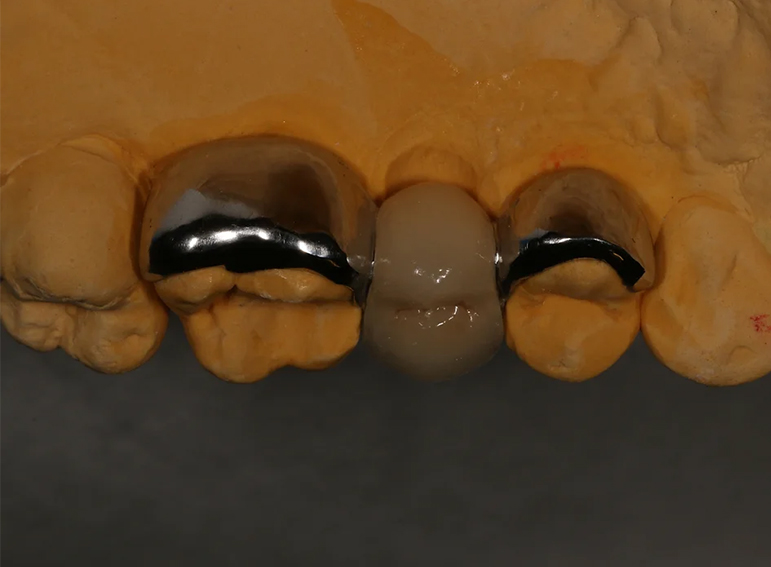

Removal of infected premolar and replacement with a temporary adhesive bridge and implant.